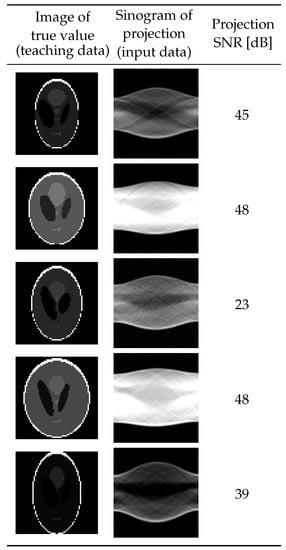

In this section, we present the results of an experiment on the proposed system using 5000 pairs of input and teaching data generated by numerical simulations. We generated teaching data in the form of -pixel images deformed by changing the attributes of each oval, i.e., its intensity, size, position, and rotation angle, from the Shepp–Logan phantom [] shown in Figure 4a. The attributes were varied in the ratio ranges shown in Table 1 from that of the base phantom by using uniform random numbers. The MATLAB (MathWorks, Natick, MA, USA) function phantom [] generated the images. To avoid generating extremely large or small ovals that should not be considered, some common deformation rates were chosen for one attribute in some of the sets of ovals in one phantom. The input data were projections calculated by Equation (1) by using a common projection operator A, projection noise , and the target image x as the corresponding teaching data. The projection operator A, represented as a matrix, was simulated on the basis of the Radon transform assuming parallel projections from 90 directions with 95 detectors, so and . The signal-to-noise ratio (SNR) for each projection was selected so as to be uniformly distributed in the range of 20 dB to 50 dB. Figure 5 shows the resulting experimental histogram of SNRs, while Figure 6 shows samples of learning data generated by the above procedure.

Figure 6.

Samples of learning data.